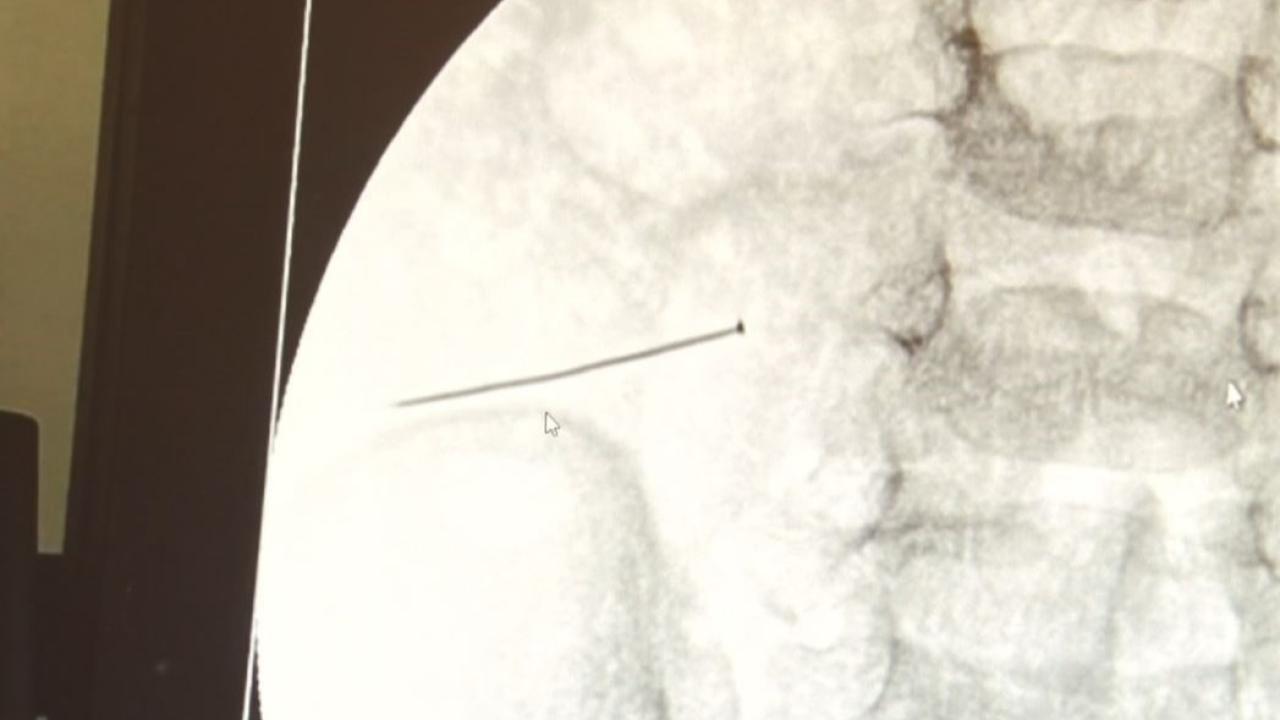

Öte yandan, yaklaşık 3 santimlik toplu iğne filme yansıyan görüntüsüyle gözler önüne serildi.

Çocuklarda yabancı cisim yutulmasına yönelik konuşan ve hastasına ilişkin bilgi veren Doç. Dr. Sefa Sağ, "Soluk borusuna kaçması durumunda çocuğun Allah göstermesin ölümüyle veya ömür boyunca yatağa bağımlı kalmasıyla neticelenebilecek sonuçlar doğurabiliyor. Yutulması durumunda da gastrointestinal sistemin herhangi bir yerine takılmadığı müddetçe ekseriyâ yabancı cisimlerin dışarıya çıkmasını bekliyoruz. Yabancı cisim yutulmasını 2 grupta inceleyebiliriz. Sıvı ve katı cisimler olarak sıvı; evde kullanılan kimyasal temizlik malzemelerinin yutulması çok ciddi problemler oluşturabilmekte. Ağızda, yemek borusunda ve midede yanıklar meydana getirebilmekte. Uzun dönemde çocukların hayat kalitesini oldukça etkileyen sonuçlar doğurabilmekte. Katı cisimlerden de ekseriyâ kendiliğinden çıkmasını bekleriz ancak böyle delici, kesici aletlerin yutulmasında ise herhangi bir bağırsağın veya gastrointestinal sistemin bir parçasında delinmeler meydana getirebiliyor. Bu çocuğumuzda da aynen böyle bir hadise meydana gelmişti. Sanırım 1 gün önce ailenin yuttuğunu tahmin ettiği bir yabancı cisim; toplu iğne. Ertesi gün bağırsakta delinmeyle sonuçlanmış ve çocukta da ciddi semptomlar meydana getirmişti. Bu şekilde hasta bize başvurdu. Tetkikler sonucunda yabancı cismi tespit ettik, semptomları ve bulgularına göre de çocuğu ameliyata aldık. Yaklaşık 3 santim boyunda bir toplu iğnenin ince bağırsağı deldiğini, ince bağırsaktaki içeriğin de karın içerisine dolduğunu gördük. Ameliyatı başarılı bir şekilde tamamladık, yaklaşık 1 saat süren bir ameliyattı" dedi.